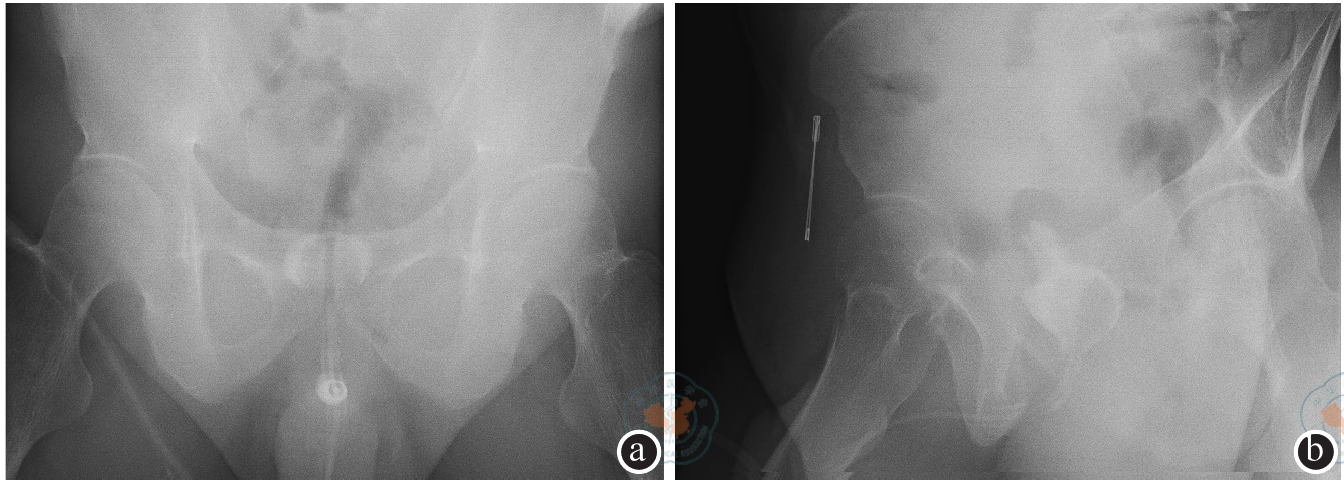

图2 氯胺酮相关性膀胱炎患者回肠代膀胱扩大术后6个月膀胱造影注:膀胱形态不规则,边缘不光滑,膀胱容量增多(图a和b分别为腹部正位片和侧位片)